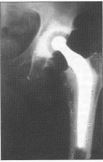

You will need to be fasted for 8 hours before the operation so as to be able to safely receive an anaesthetic. Depending on where and how complex the break is in your hip, there will be different operations to deal with the fracture. If the neck of the ball part of your hip is broken we would most commonly recommend half a hip replacement (Figure 1).

Figure 1 - Thompson’s prosthesis

If the break has left a good blood supply to the ball part of the joint we can fix this with metal screws and a plate (Figure 2).

Figure 2 - Dynamic Hip Screw